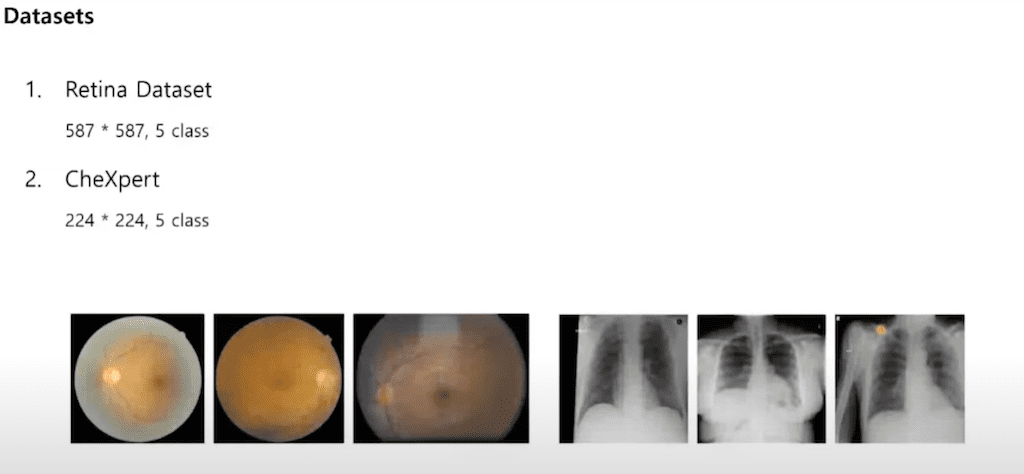

본 논문에서는 실험의 Retina 데이터셋과 CheXpert라는 Che x-ray 데이터셋을 사용했습니다. 그 데이터셋 모두 5 class를 가지고 있고 보통 task에 관계없이 ResNet같이 큰 모델들을 사용을 합니다. 본 논문에서는 이런 Standard 한 모델과 직접 설계한 작은 모델을 비교했습니다.

저자는 작은 모델에서의 Transfer learning에 대한 연구가 아직까지 거의 없었다고 합니다. 그리고 Standard 모델의 파라미터들 즉, 출력과 가까운 layer의 파라미터들은 ImageNet 데이터셋의 1000개의 클래스를 분류하기 위해 학습됩니다. 보통 Retina 데이터셋이나 Chex 데이터셋같이 실생활에 있는 데이터셋들의 경우 클래스가 많지 않기 때문에 이런 Standard 모델의 파라미터는 과할 수 있다고 합니다.